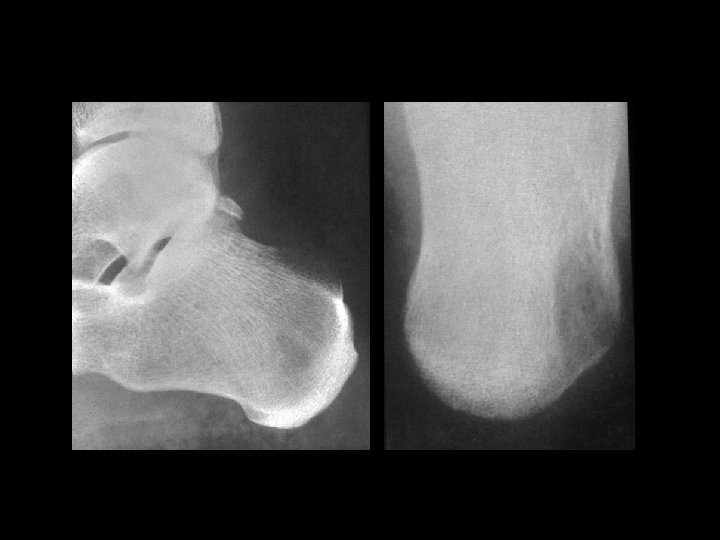

Calcaneal UBC • Findings: – Central lucent lesion within the calcaneous – Fine sclerotic margin • ddx: – Intraosseous lipoma